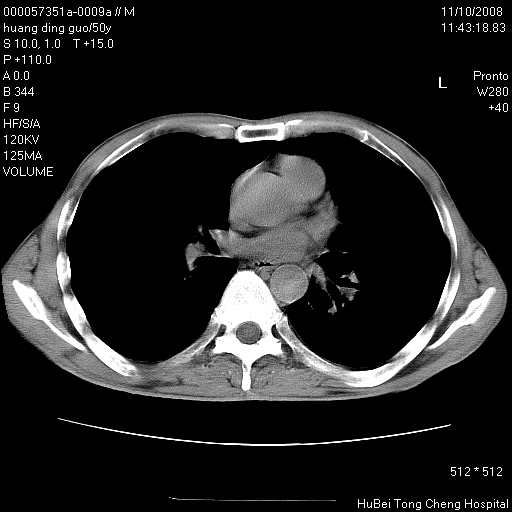

患者 男,50岁。左侧腰背部疼痛3月余,伴消瘦。平素健康,无传染病史。

胸部ct轴位平扫(层厚10mm,螺距1.5,重建间隔10mm),图像如下:

左肺下叶背段有一厚壁空洞,外壁呈锯齿状伴毛刺改变。空洞相邻胸膜有牵拉改变。左肺下叶血管支气管束不规则增粗,小叶间隔增厚。胸椎骨质破坏。考虑左肺下叶周围型肺癌伴左肺下叶癌性淋巴管炎、胸椎转移。

左肺下叶背段有一厚壁空洞,外壁呈锯齿状伴毛刺改变。空洞相邻胸膜有牵拉改变。左肺下叶血管支气管束不规则增粗,小叶间隔增厚。胸椎骨质破坏。考虑左肺下叶周围型肺癌伴阻塞性肺炎、胸椎转移。其他待排

左肺下叶背段有一厚壁空洞,内壁不规则,外壁呈锯齿状伴毛刺改变。空洞相邻胸膜有牵拉改变。周围呈絮状炎性改变,左肺下叶血管支气管束不规则增粗,小叶间隔增厚。胸椎骨质破坏。考虑左肺下叶周围型肺癌伴左肺下叶阻塞性肺炎、胸椎转移。